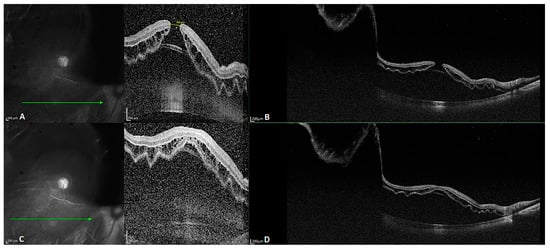

Biomedical optics requires imaging at a wavelength of 600 to 1000 nm, as tissue absorption is low within this range. SD-OCT is mainly performed at a wavelength of 800 to 900 nm. SS-OCT is mainly performed in the near-infrared radiation spectrum, at wavelengths of 1020 to 1080 nm, as the water absorption coefficient is low at a wavelength of 1060 nm [], which contributes to better imaging of tissues with a low water content. The improved penetration depth of SS-OCT with less scattering is attributable to its longer wavelength used for imaging. The images in Figure 3 were obtained for a patient with refractive medium turbidity and a macular hole. On the SD-OCT images, the retina and choroidal folds are visible over a certain range, whereas the SS-OCT images display everything from the vitreous to the choroid layer. Currently, most SS-OCT instruments are based on VCSELs, which have a coherence length exceeding 100 mm. Coupled with high-speed data acquisition, they allow steady imaging at a depth of 45 mm in tissue. Therefore, SS-OCT provides a 16 mm field of view in full-eye imaging, as illustrated in Figure 4. This is also the basis for the 3D imaging of the anterior segment.

Figure 3.

B-scan images of a patient with slightly refractive medium turbidity and a macular hole. (A,C) SD-OCT images revealing a macular hole and a part of the detached retina; the choroid is not visible because the retina detachment is too high. (B,D) SS-OCT images with a depth of 6 mm and width of 24 mm, clearly visualizing the retinal detachment, as well as the choroid and part of the sclera.